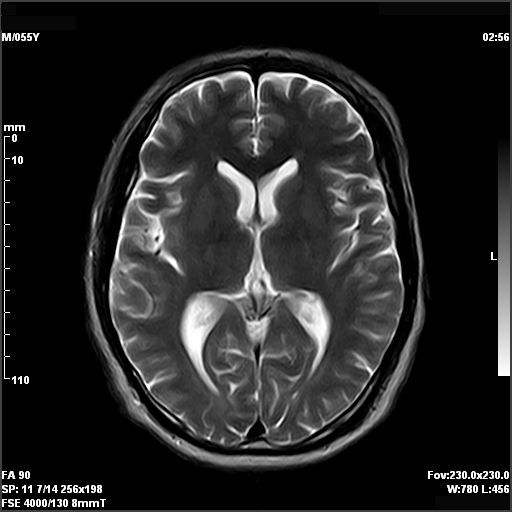

From health.ucdavis.edu

Brain and Spine MRI Spectrometer Mri Find out how mrs can help in the diagnosis of diseases of the brain and other parts of the body. Mr spectroscopic imaging (mrsi) has become a valuable tool for quantifying metabolic abnormalities in human brain, prostate, breast and other organs. Learn about mrs, a diagnostic imaging technique that measures the concentration of specific chemicals in tissues. Today mrsi allows. Spectrometer Mri.